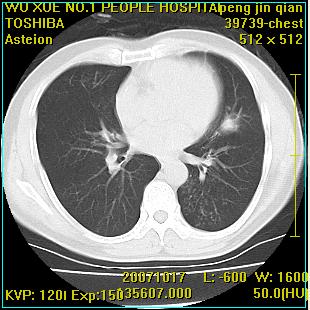

标题: CT10148:男,56岁,咳血。 [打印本页]

标题: CT10148:男,56岁,咳血。

右肺下叶背段/左上肺/左下肺结核伴空洞形成

结核 空洞伴两肺播散

浸润型肺结核伴左上肺空洞形成,两肺播散灶